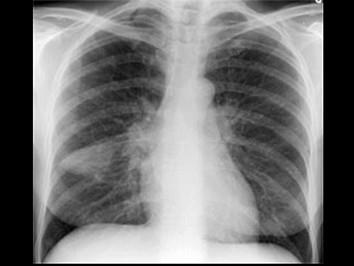

问题 女性,52岁,因四肢关节疼痛、肢端肥大2个月,经各种治疗无缓解。X线胸片如图。支纤镜检查阴性。最可能的诊断是 ( )

选项 A、肺脓肿 B、以上均不是 C、肺炎合并肢端肥大症 D、肺癌 E、肺结核合并风湿性关节炎

答案 D